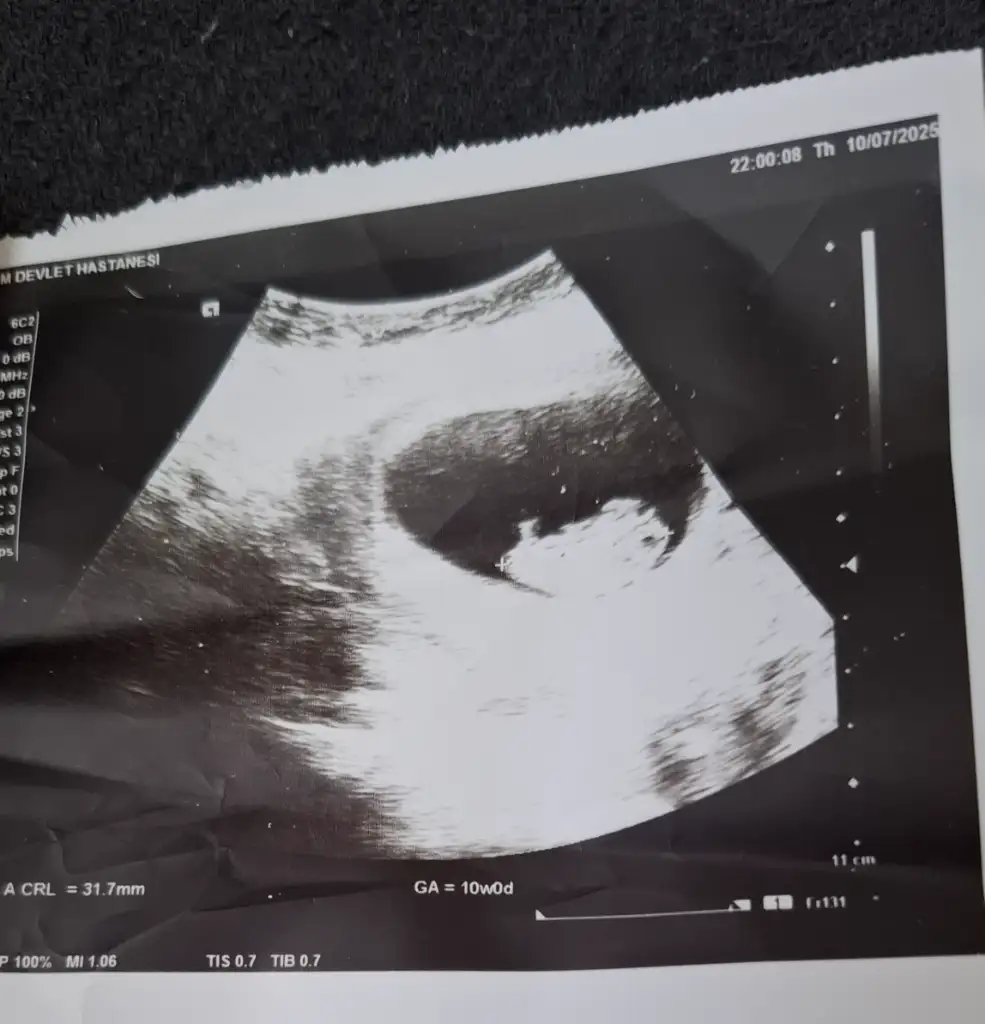

Banada bakarmisiniz

Rica etsem Banada tahminde bulunurmusunuz 9+1 karından ultrason